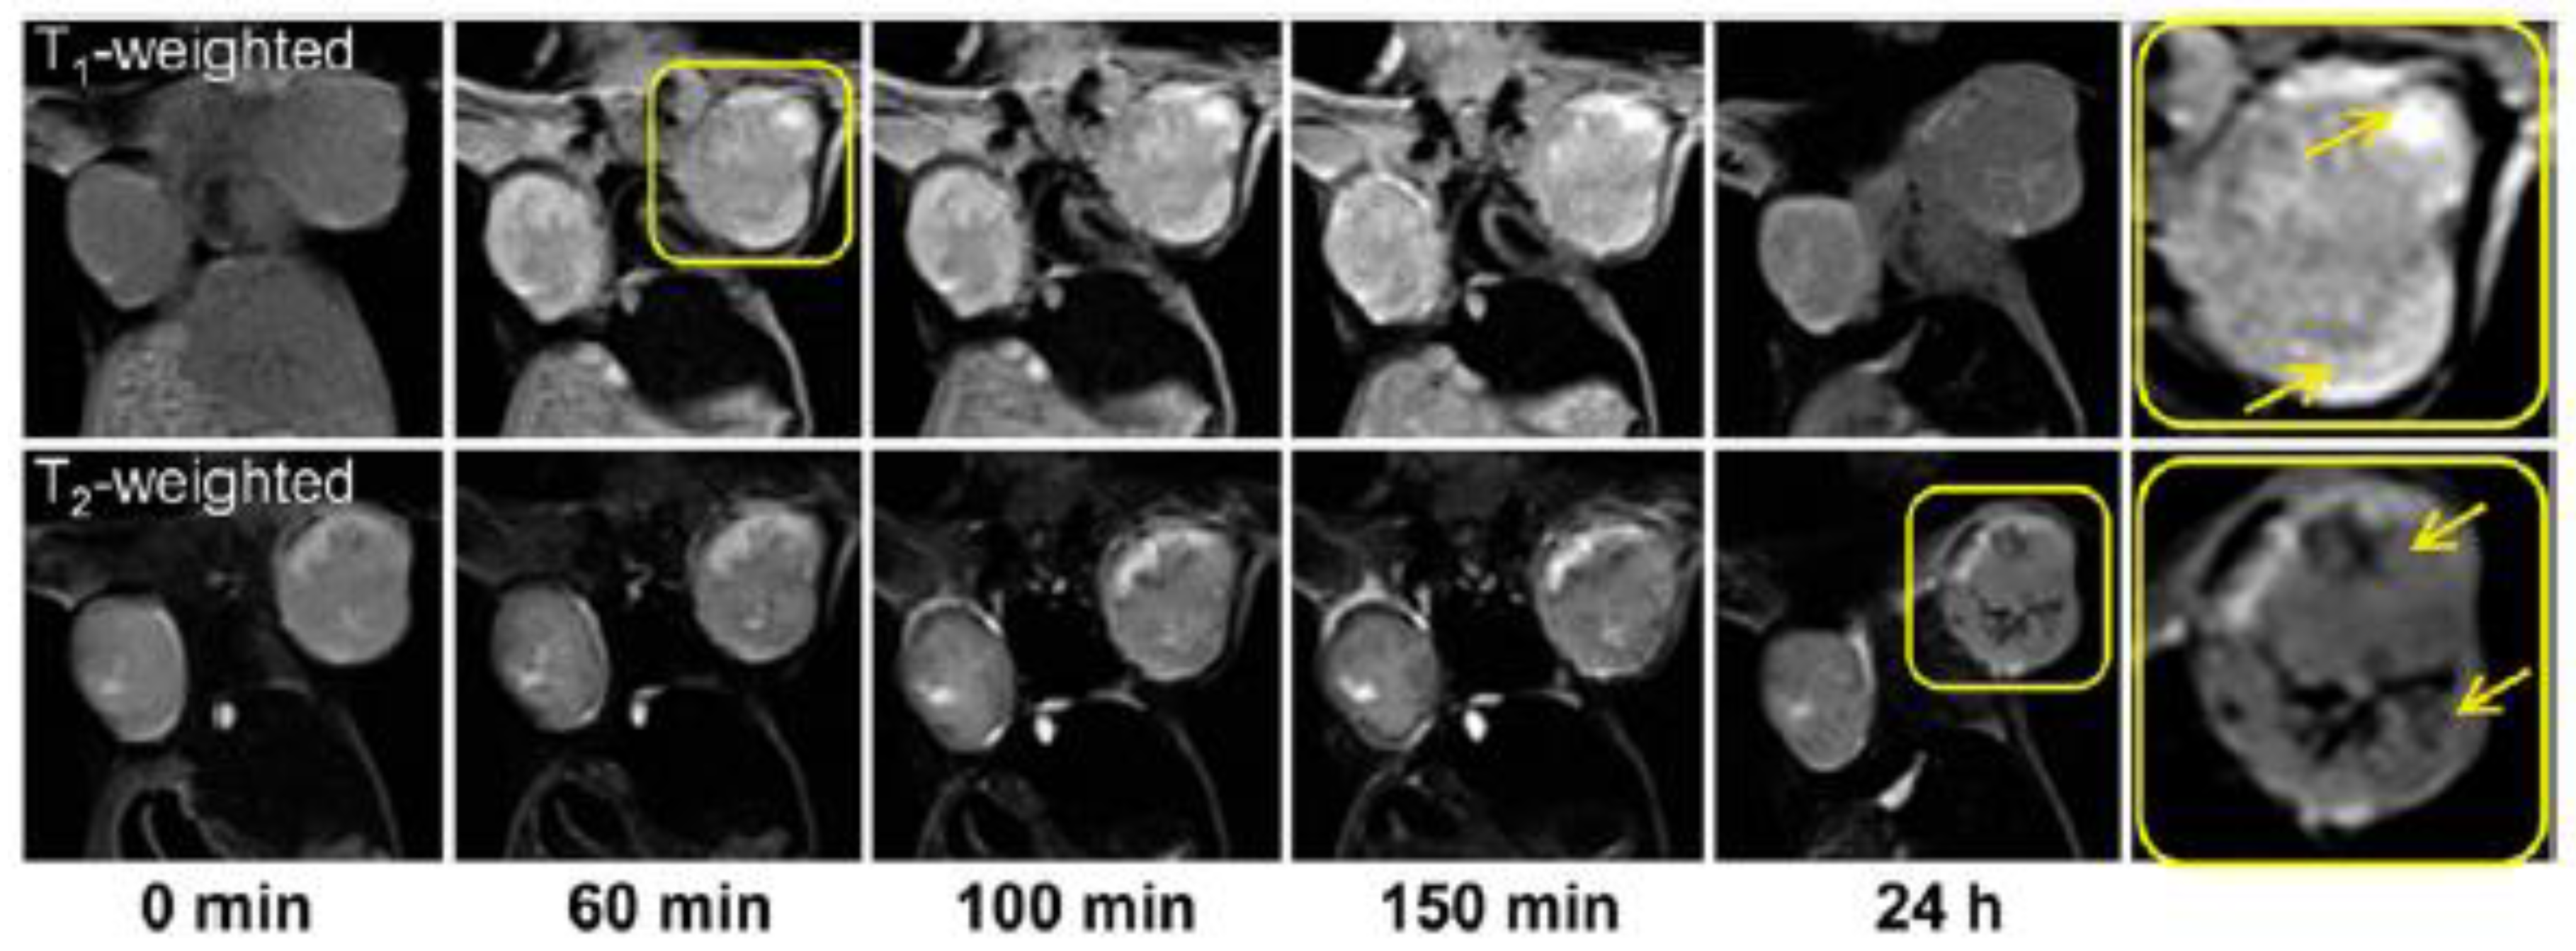

Gadolinium, a paramagnetic ion with the largest number of unpaired electrons, is the most effective T1 contrast agent, which has however the main drawback of being toxic. Although it is always used in combination with chelating molecules with the aim of avoiding its potential risk, alternative strategies are seeking to exploit new aspects of SPIONs to produce versatile dual contrast agents, taking advantage of the existing SPION (Ferucarbotran (Resovist®), Bayer Healthcare) clinically approved as MRI contrast agent. Ultra-small magnetite NPs with a diameter around 3.5 nm have been studied as candidates for dual-modal MRI contrast with simultaneous T1/T2 switching, activity [104]. In this study, the observed switching between T1−T2 contrast (see Figure 17) is ascribed to the fact that ultra-small SPIONs are single-dispersed in blood and produce T1 contrast, while after their extravasation and accumulation in the tumoral site, the NPs’ self-assembling into larger clusters induces the appearances of T2 contrast modulated by magnetic interactions.

T1- and T2-weighted MRI of a mouse bearing orthotopic 4T1 tumors before and after i.v. administration of ultra-small SPIONs at different time points. Bright contrast with increasing signal in T1-weighted MR images was observed in the tumor, particularly peripheral regions (inset), at early time points (i.e., 5–150 min) resulting from the single-dispersed ultra-small SPIONs, whereas signals in several regions of the tumor turning dark (arrow indicated) were observed in T2-weighted images 24 h after ultra-small SPIONs injection because of ultra-small SPIONs clustering in the tumor interstitials. (Image reprinted with permission from [104], ACS, 2017).